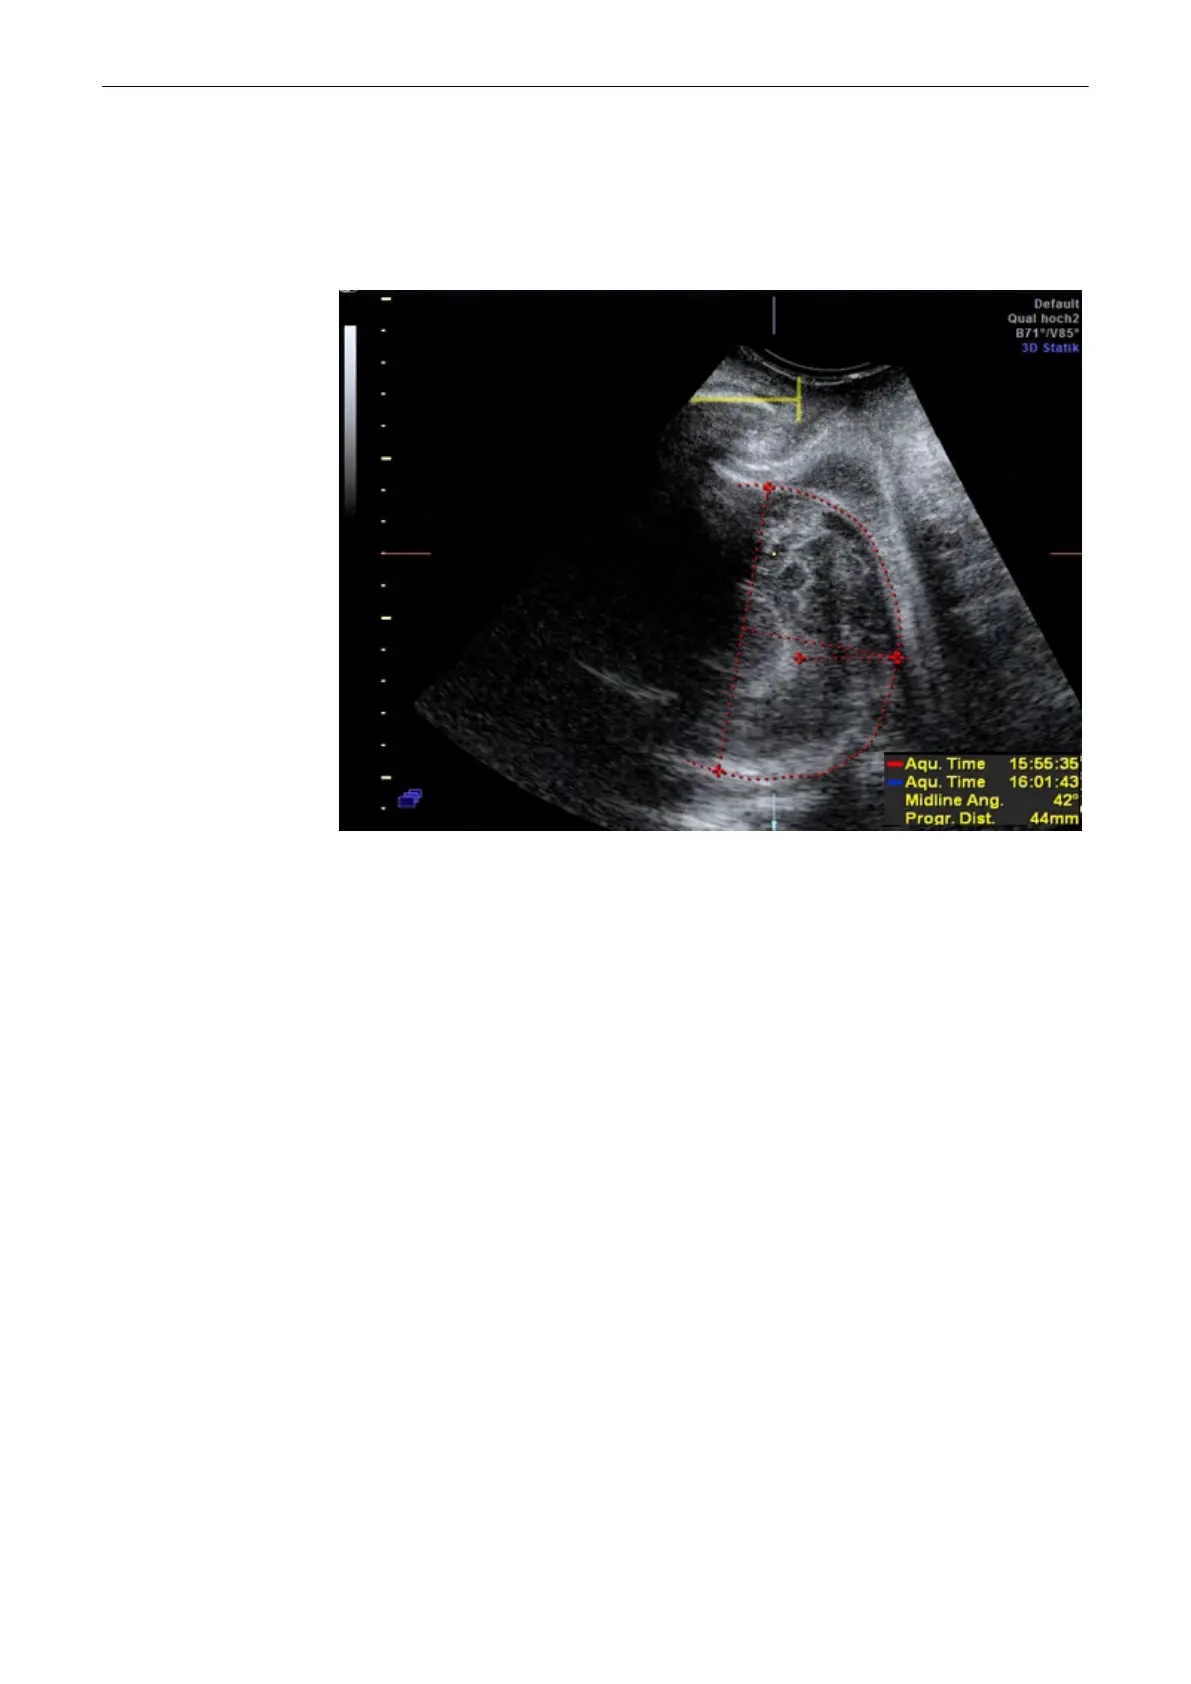

9.15.7 Head progression distance

Perform this measurement in image plane A. The measurement’s point of origin is vertically

locked to the pubis. Mark the distal point of the fetal head to measure the distance between

the pubis and the head in millimeters.

9.15.8 Head progression angle

Perform this measurement in image plane A. Starting from the center of the pubis, set the end

point that the dashed line is tangent to the fetal head. The resulting measurement is the